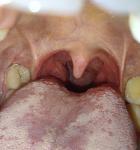

Увеличена миндалина с правой стороны

Здравствуйте, примерно пол года назад стала ощущать в горле будто скапливается много слизи, особенно после приема пищи, постоянно хочется откашлянуться (но ничего не выделяется при кашле). Посмотрела в зеркало горло и увидела с правой стороны сильно увеличена миндалина (фото прилагаю). Ангиной раньше часто болела. Что это может быть? Нужно бежать к доктору? Спасибо за ответ.

Здравствуйте. На фото признаки Хронического тонзиллита.

Здравствуйте. Со стороны ЖКТ проблем нет. А вот нос одна половина (правая) закладывает но только к вечеру, днём вроде нормально дышу. Чтобы что-то стекало по задней стенке не чувствую. Можете что-то посоветовать? Спасибо большое что ответили.

1. . Полоскание горла раствором морской соли – пол чайн ложки на 250 мл кип воды х 2 раза в деньш после еды – утром и вечером, сразу после полоскания спрей в горло МИРАМИСТИН – 7 дней

2. Тонзилгон по 2 таб х 3 раза в день 10 дней внутрь

3. Полиоксидоний 12 мг – 1-2 таб рассасывать во рту 10 дней:

4 Промывание лакун миндалин курсами по 3-5 процедур через день